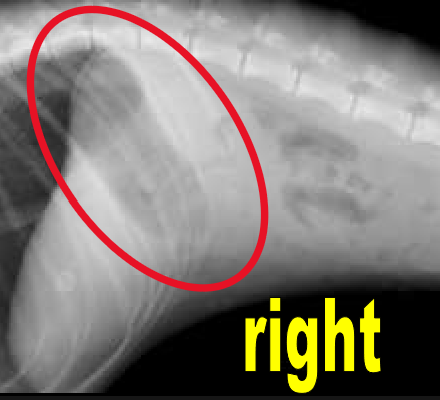

Serosal Detail

contrast between abdominal organs and the ability to see their edges

Border effacement

2 structures of the same opacity are in contact, so their margins cannot be distinguished